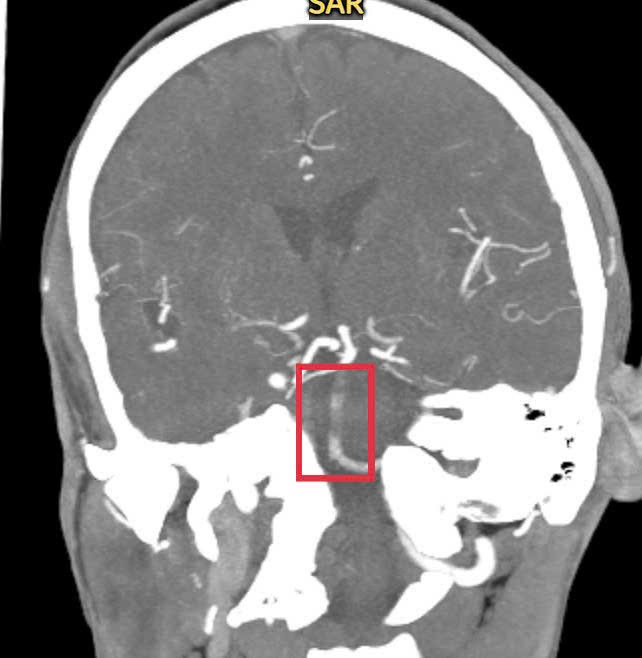

| Hình ảnh kiểm tra ghi nhận bệnh nhân bị đột quỵ do tắc động mạch thân nền |

Sau khi tiêm thuốc, theo quy trình cấp cứu đột quỵ, bệnh nhân được chụp lại phim CT mạch máu não có thuốc cản quang, các bác sĩ phát hiện người bệnh có tình trạng tắc động mạch thân nền. Đây là động mạch rất quan trọng nuôi vùng thân não và đột quỵ do tắc động mạch thân nền là thể đột quỵ có nguy cơ tử vong lên đến 90% nếu không được phát hiện sớm và cấp cứu kịp thời.